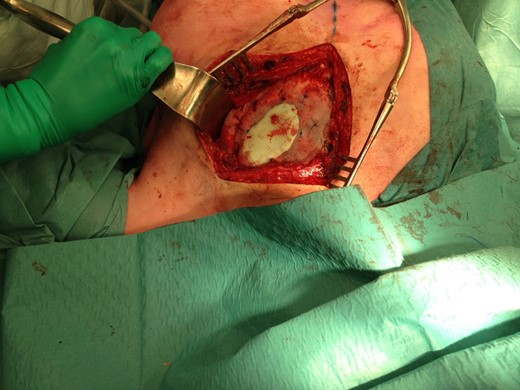

The size of the thoracic wall defect following resection measured 8 by 5.5 cm A patch was prepared using two polypropylene meshes and interpolate of methyl methacrylate (Fig. 3). The patch was placed and tightened to the periosteum using prolene sutures (Fig. 4). Figure 5 shows the resected tumour. Finally, subcutaneous tissue and skin were closed in layers using a Vicryl and intracutaneous Monocryl suture.

Positioning of the mesh and fixation to the periosteum of adjacent ribs.

The resected tumour. Marking: short, cranial side; long, lateral side.

Pathology examination of the specimen was performed by an expert bony tumour panel. Definitive pathology of the specimen revealed FD that was radically removed. At follow-up 6 weeks later on the outpatient clinic, the patient was in good health. The wound had healed properly and complaints of chronic cough had stopped.